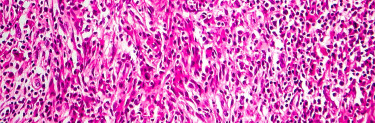

În cadrul limfomului non-Hodgkin, o parte dintre celulele albe, numite limfocite, se multiplică în mod necontrolat și pot alcătui formațiuni tumorale în corp.

Majoritatea limfoamelor non-Hodgkin iau naștere din populația de limfocite B. Acestea au rolul de a lupta împotriva infecțiilor producând anticorpi pentru a neutraliza microorganisme ce invadează organismul. Limfoamele non-Hodgkin care implică celule B includ: limfomul de tip B difuz cu celule mari, limfomul folicular, limfomul cu celule în manta, limfomul Burkitt.

Limfoamele non-Hodgkin își pot avea originea și în populația de limfocite T, însă mult mai rar. Limfocitele T au rolul de a distruge celulele străine prin mecanism direct. Limfoamele non-Hodgkin care implică celule T includ: limfonul cu celule T periferice, limfomul cutanat cu celule T.

Pentru stabilirea tipului exact de limfom, pacienții au acces la examinări de anatomie patologică, inclusiv biopsii, analize histopatologice și examene imunohistochimice, prelucrate în Laboratorul de Anatomie Patologică SANADOR. Planul de tratament este stabilit individualizat, unde o echipă multidisciplinară de medici cu experiență colaborează pentru a oferi cele mai potrivite soluții terapeutice, adaptate fiecărui pacient.